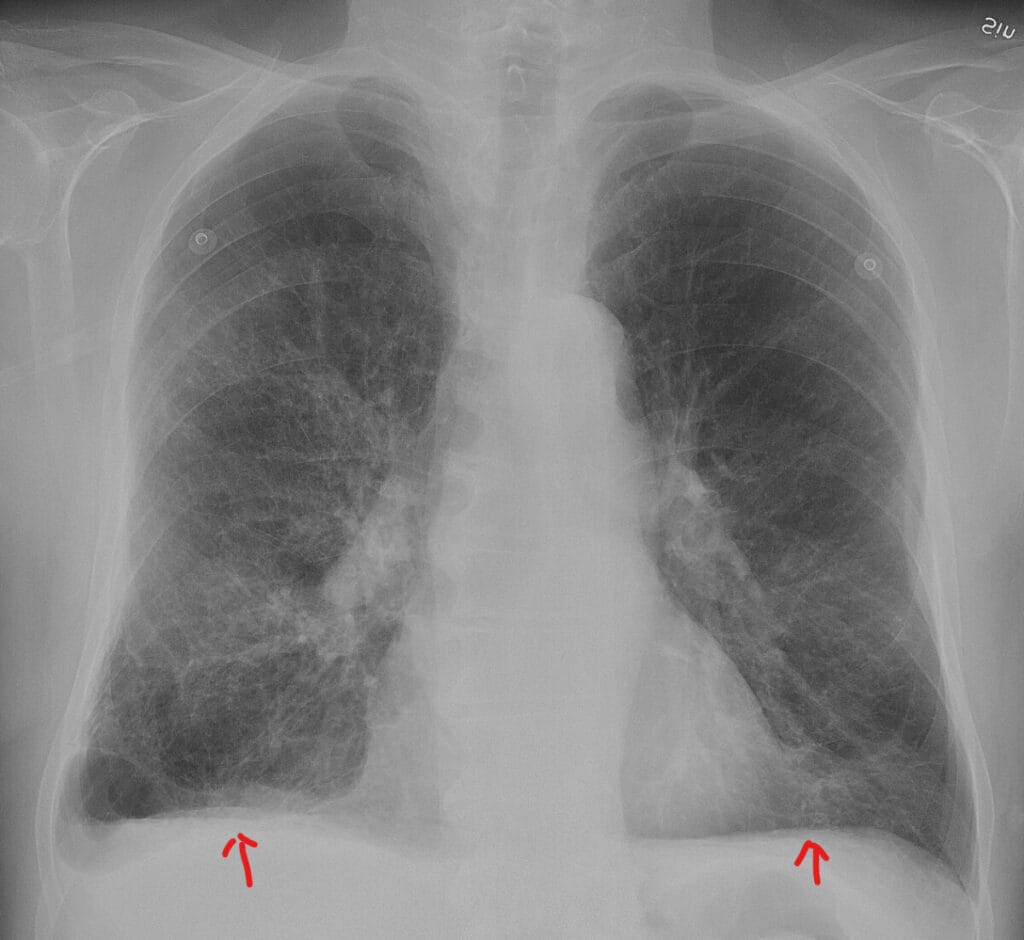

| ✅ 영상 검사(X-ray)에서는 – 폐의 과팽창(hyperinflation) – 전후직경 증가(AP diameter 증가) – 횡격막의 평탄화(flattened diaphragm)가 관찰됩니다 |